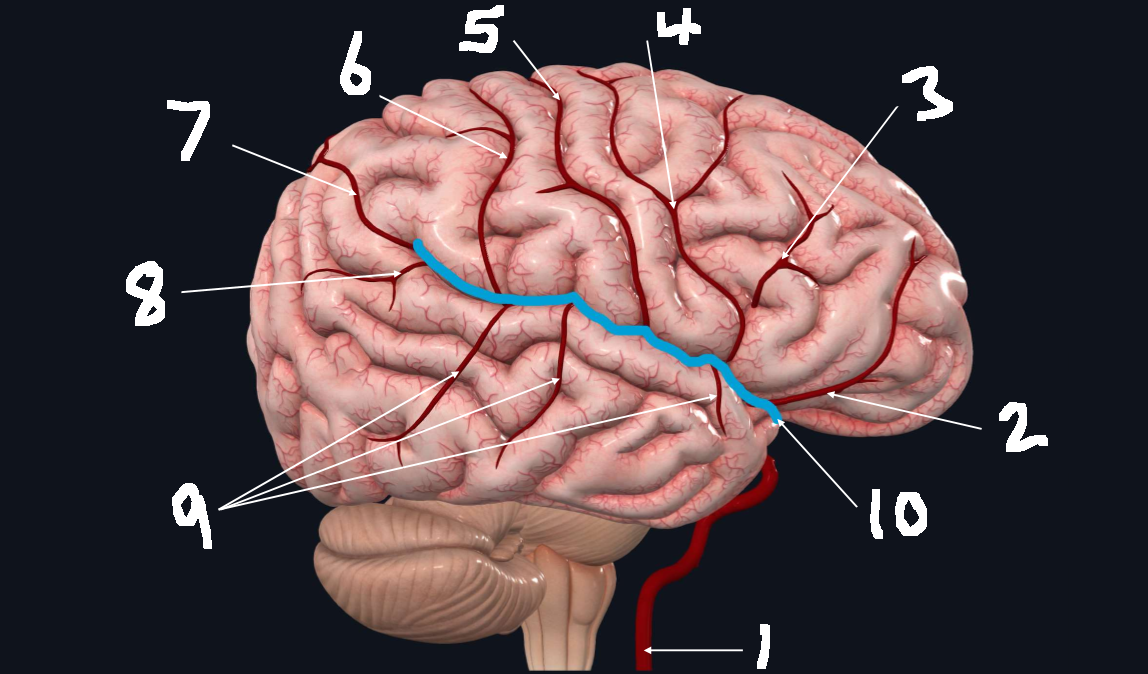

What is 1?

internal carotid artery

What is 2?

orbitofrontal artery

What is 3?

prefrontal artery

What is 4?

precentral artery

What is 5?

central artery

What is 6?

postcentral artery

What is 7?

posterior parietal artery

What is 8?

angular artery

What is 9?

temporal arteries (anterior, middle, posterior)

What is 10?

lateral cerebral fissure